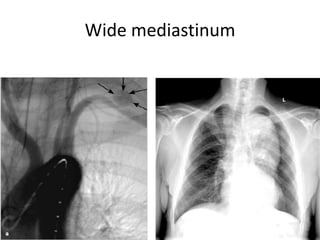

Chest x-ray : widened mediastinum, frac. Rib 1,2

Wide mediastinum

• widening of mediastinum on chest X-ray;